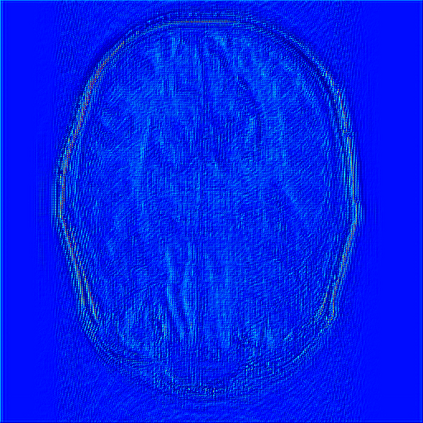

Reconstructing magnetic resonance (MR) images from undersampled data is a challenging problem due to various artifacts introduced by the under-sampling operation. Recent deep learning-based methods for MR image reconstruction usually leverage a generic auto-encoder architecture which captures low-level features at the initial layers and high?level features at the deeper layers. Such networks focus much on global features which may not be optimal to reconstruct the fully-sampled image. In this paper, we propose an Over-and-Under Complete Convolu?tional Recurrent Neural Network (OUCR), which consists of an overcomplete and an undercomplete Convolutional Recurrent Neural Network(CRNN). The overcomplete branch gives special attention in learning local structures by restraining the receptive field of the network. Combining it with the undercomplete branch leads to a network which focuses more on low-level features without losing out on the global structures. Extensive experiments on two datasets demonstrate that the proposed method achieves significant improvements over the compressed sensing and popular deep learning-based methods with less number of trainable parameters. Our code is available at https://github.com/guopengf/OUCR.